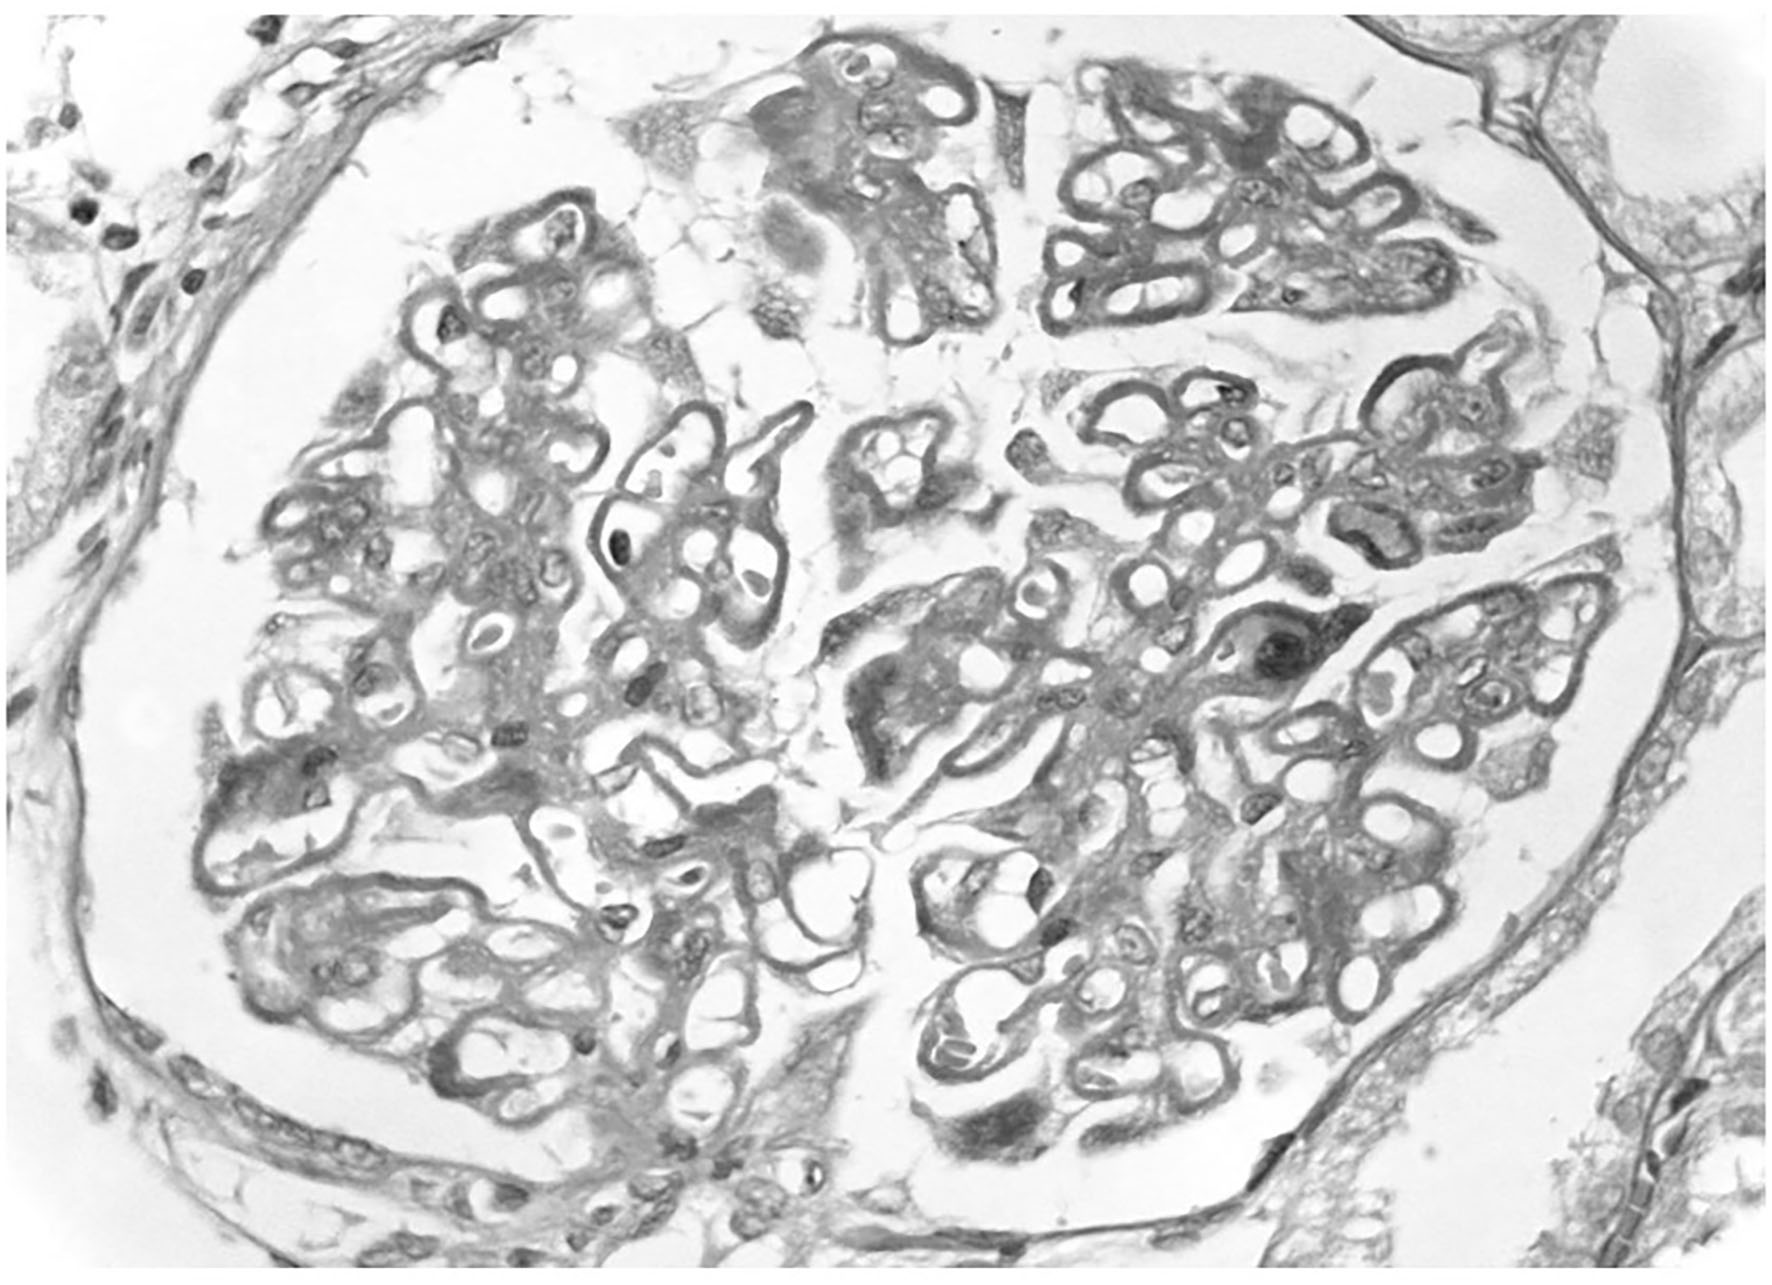

Figure 1

Primary membranous nephropathy. A light microscopy there is diffuse thickening of glomerular capillary walls due to the presence of many immunedeposits in subepithelial position.